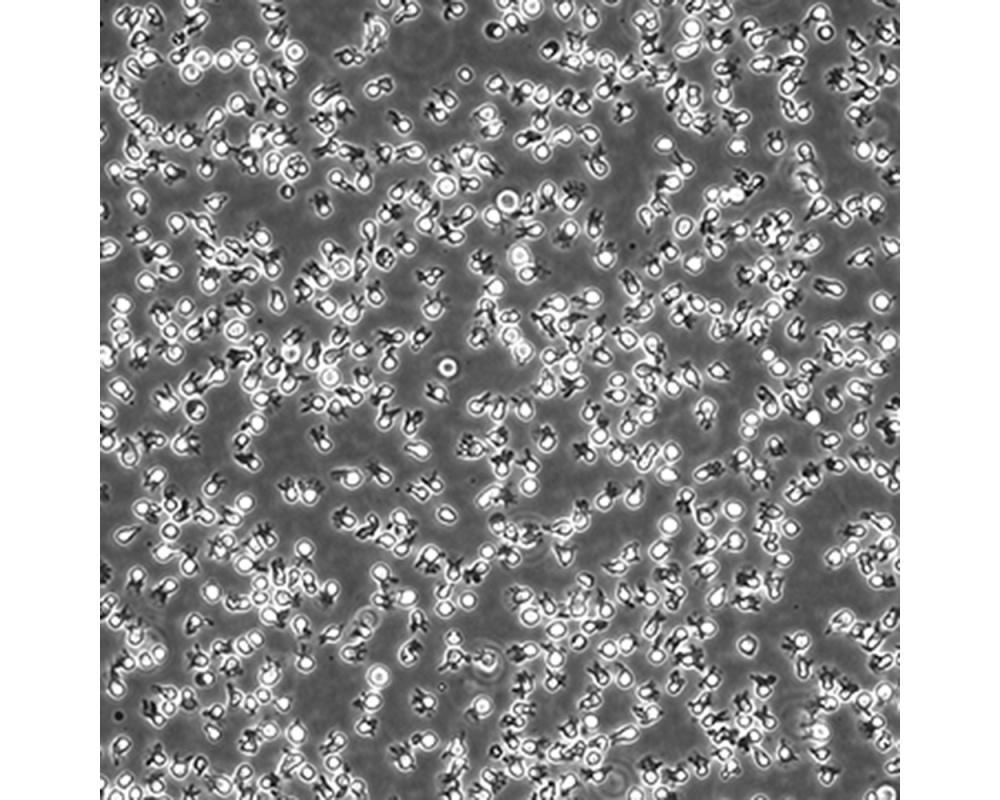

中文名稱 人彌漫大B細(xì)胞淋巴瘤細(xì)胞

組織來源 彌漫大B細(xì)胞淋巴瘤;男性

生長特性 懸浮

培養(yǎng)基 IMDM,90%;FBS,10%;雙抗。

傳代方法 Maintain cultures at a cell concentraion between between 1 X 10(5) and 1 X 10(6) viable cells/ml.

培養(yǎng)條件 Atmosphere: Air, 95%; CO2, 5%。Temperature: 37℃